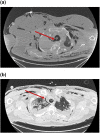

Tracheal trauma after difficult airway management in morbidly obese patients with COVID-19

Keywords: ARDS; COVID-19; ECMO; airway management; obesity; pneumomediastinum; tracheal perforation.